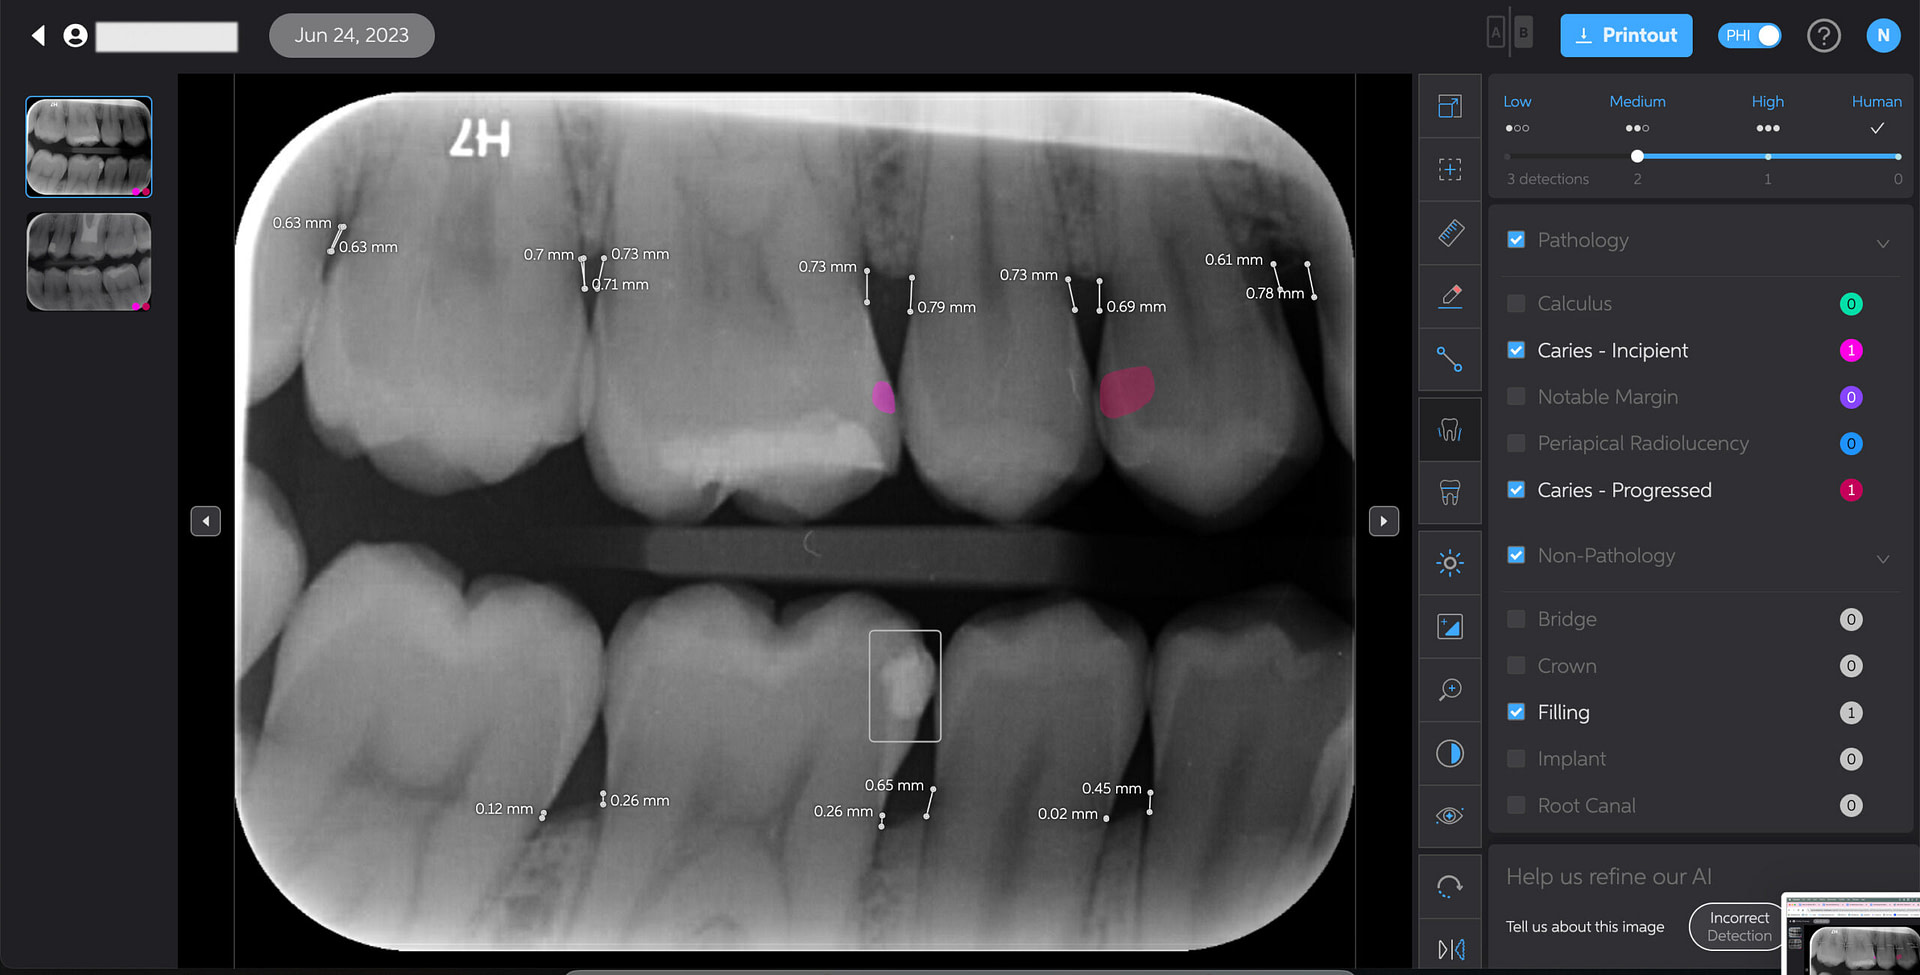

Caries Detection

The best for last and arguably the most well-thought-out feature. Especially with the tooth segmentation mode, which makes it easier for patients to understand their diagnosis and treatment plans.

The system uses two shades of pink to indicate potential caries:

- Light pink: Incipient caries (100% in enamel) - we will often review

- Darker magenta: Caries extending into dentin - we need to restore

The system even provides a percentage breakdown of enamel vs. dentin involvement. I have been blown away by its accuracy while using it, and it makes something that feels quite subjective (reading shades of grey) into a science.

This feature is very useful for patient education and deciding between preventive measures and restorative treatment. However, remember that radiographic evidence alone is not always sufficient for a definitive caries diagnosis.

Bone Measurements

The system provides automated measurements from the crest of the bone to the cementoenamel junction (CEJ). These measurements are color-coded to indicate severity:

- White: 0-2.5 mm

- Yellow: 2.5-4 mm

- Amber: >4 mm

This feature is helpful for periodontal assessments, streamlining the process of identifying areas of bone loss. However, it's important to note that image angulation can affect the accuracy of these measurements, a limitation the system acknowledges.